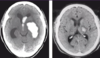

DX?

Infarto cerebral debido a ACM izq